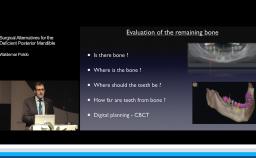

- Surgical considerations regarding the type of bone augmentation procedure and the timing of implant placement.